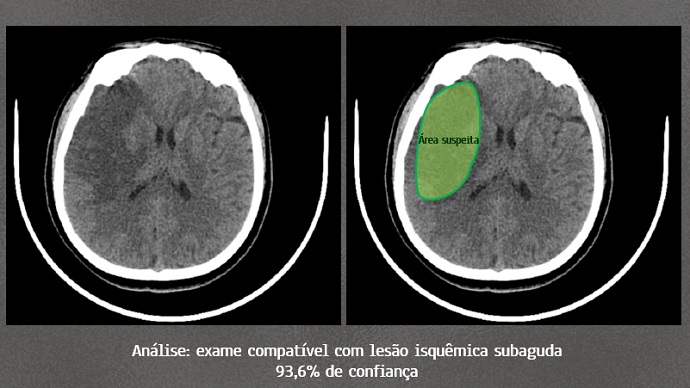

Cientistas da UFPR treinam Inteligência Artificial para apoiar diagnóstico de AVC

Pesquisadores do curso de Medicina da Universidade Federal do Paraná (UFPR) estão desenvolvendo um algoritmo capaz de identificar a probabilidade de existir um acidente vascular encefálico em tomografias de crânio. A ferramenta auxiliará o médico clínico na conclusão de um diagnóstico mais preciso de forma mais rápida. Nos casos de derrame cerebral, a agilidade é extremamente valiosa, pois o tempo entre o surgimento dos sintomas e o tratamento da doença é um fator determinante para sequelas e para o prognóstico do paciente.

De acordo com a literatura, acidentes vasculares encefálicos são a terceira maior causa de morte no mundo. O distúrbio é provocado por uma alteração de irrigação sanguínea em uma porção do cérebro e sua evolução depende de uma série de fatores como tempo de falta de fornecimento sanguíneo, área acometida e comorbidades. O diagnóstico é feito pela correlação entre os sinais clínicos do paciente e seu exame de tomografia computadorizada de crânio. Para interpretar o exame de imagem, o clínico deve ser capaz de delimitar a região afetada de outras regiões saudáveis.

Segundo Pereira, o diagnóstico de acidente vascular encefálico por meio de imagens tomográficas pode ser desafiador para o médico devido à dificuldade de diferenciar as estruturas lesionadas de processos anatômicos normais.

Por meio de uma rede neural convolucional, algoritmo de inteligência artificial que utiliza uma série de neurônios virtuais amplamente interconectados entre si, é possível treinar uma máquina a classificar e a detectar padrões em imagens de forma rápida e automática. Os pesquisadores da UFPR estão utilizando o banco de dados de um centro de radiologia situado no município de Toledo, no Paraná, para realizar a classificação com auxílio de um médico radiologista.

Todas as imagens estão acompanhadas de laudo médico oficial para a consulta. Ao final do treinamento, a rede neural emitirá gráficos e tabelas esclarecendo sua sensibilidade e acurácia. “Espera-se que a ferramenta retorne uma acurácia superior a 80% no diagnóstico de acidente vascular encefálico”, estima Pereira.